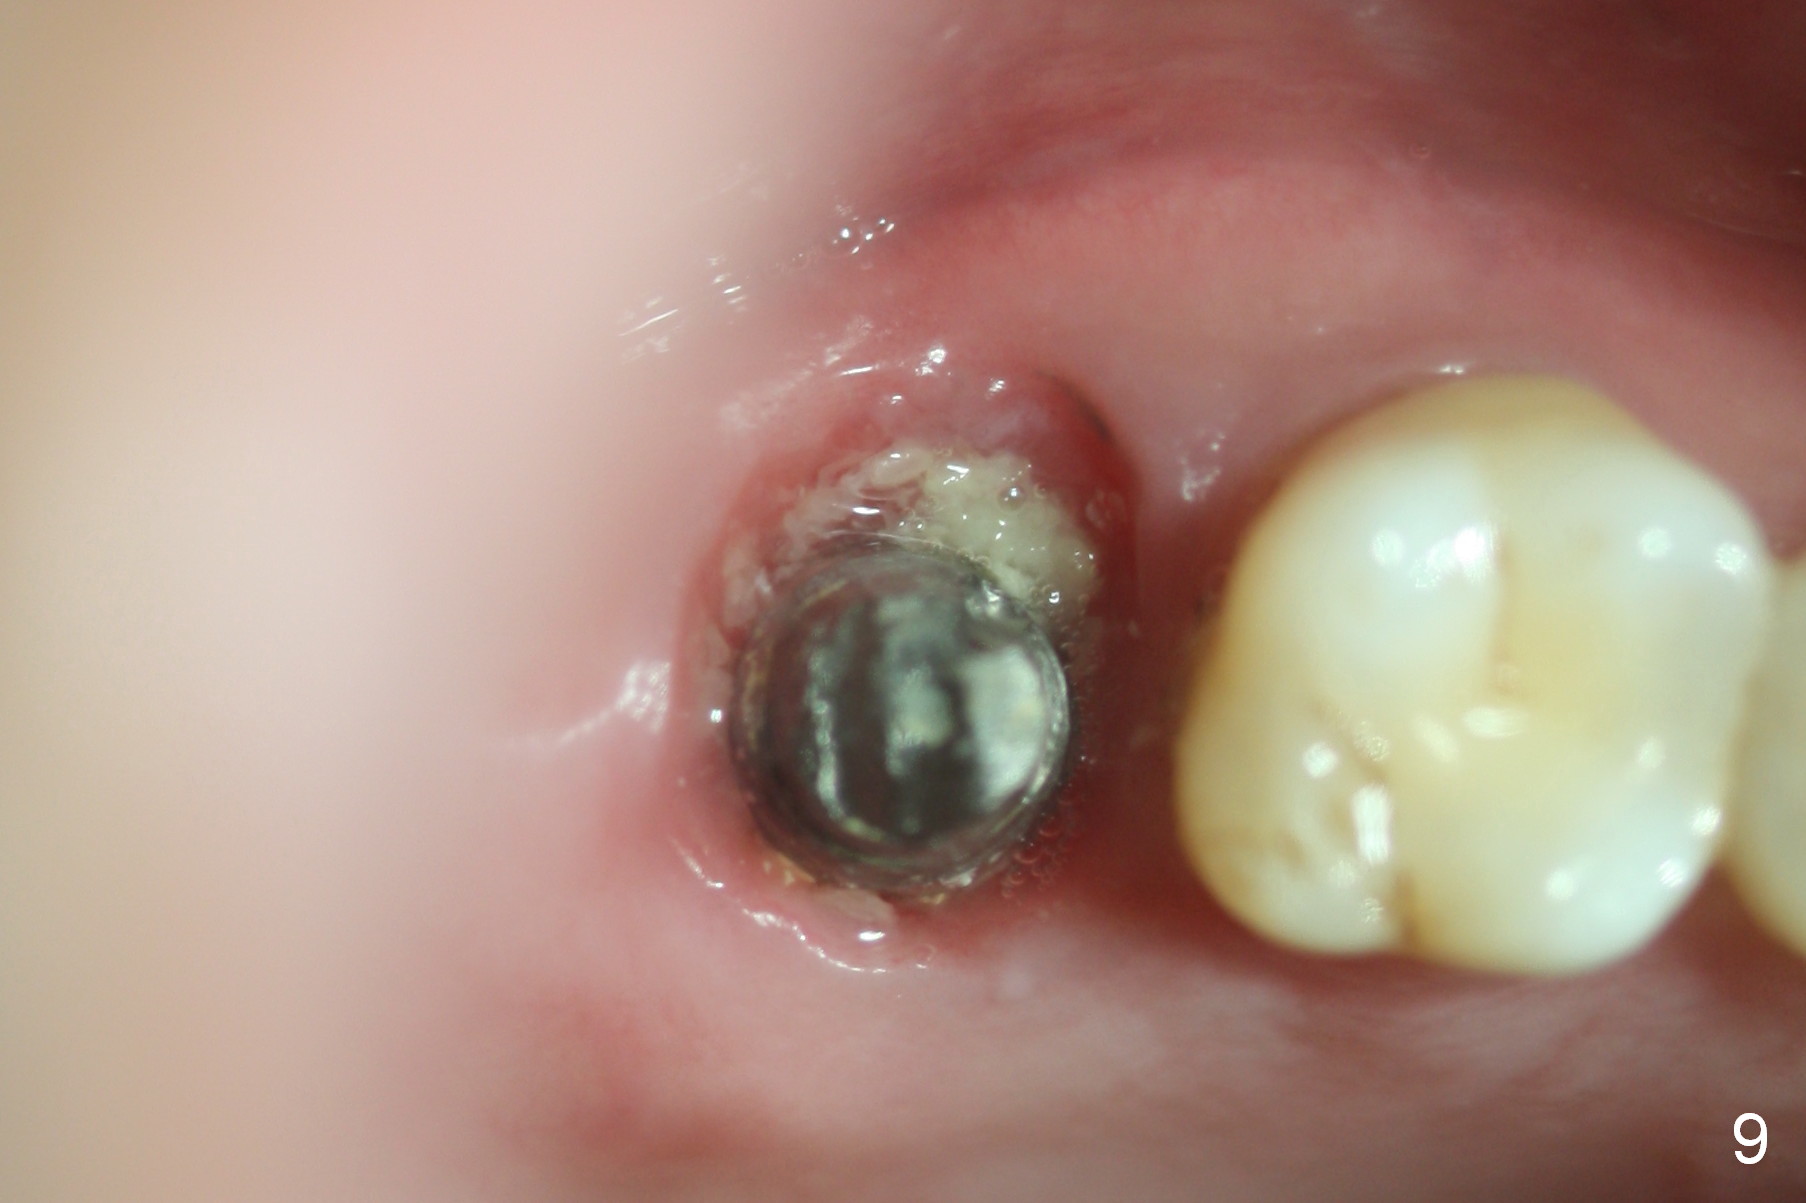

The patient returns for follow up 1 week and 1 month postop. The provisional remains in place. It is removed for margin modification 1 month postop: the bone graft having been apparently incorporating into the socket concentrically (from periphery of the socket to the implant) (Fig.9).

The provisional fractured and lost 4 months postop when the patient returned for definitive restoration. The gingiva does not seem normally when gingival retraction cords are packed.